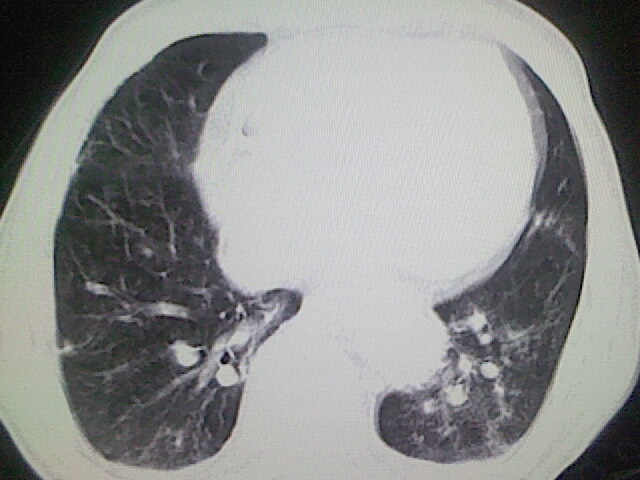

以下是引用zsl6918在2008-8-28 16:49:00的发言:[br]双肺炎性病灶,食管狭窄估计与心房增大压迫所致。

以下是引用xulianj在2008-8-28 20:36:00的发言:[br]慢支肺气肿伴感染,右上肺陈旧性结核;食道建议胃镜检查。

以下是引用wqs571018在2008-8-28 21:18:00的发言:[br]慢支继发感染,右上肺陈旧性结核;食道建议胃镜检查。